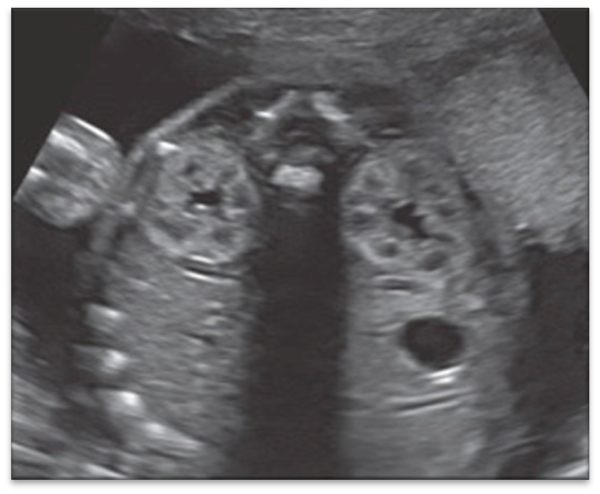

IPKD (ARPKD)

ADPKD